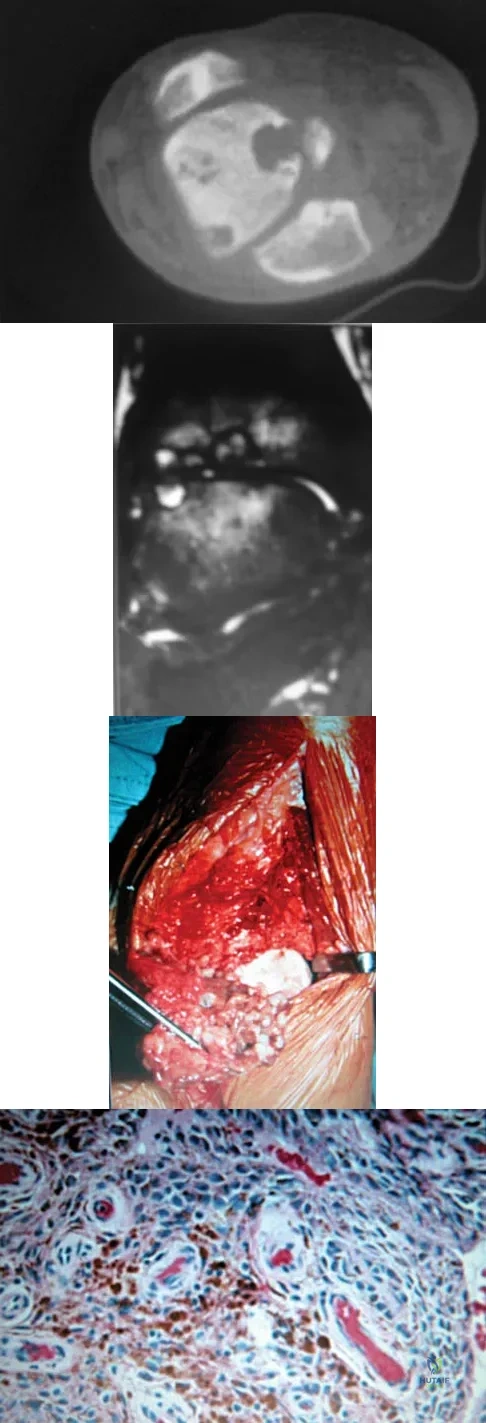

A 13-year-old boy has had pain and swelling in his ankle for the past several months. Based on the radiograph, MRI scan, and biopsy specimen shown in Figures 77a through 77c, what is the best course of action?

Explanation

A 30-year-old man has had intermittent swelling of his right ankle for the past 6 months. He denies any history of trauma. Radiographs reveal osteolytic changes on both sides of the joint. An axial CT scan and a T2-weighted MRI scan are shown in Figures 40a and 40b. He undergoes surgical excision. An intraoperative photograph and a biopsy specimen are shown in Figures 40c and 40d. What is the most likely diagnosis?

Explanation